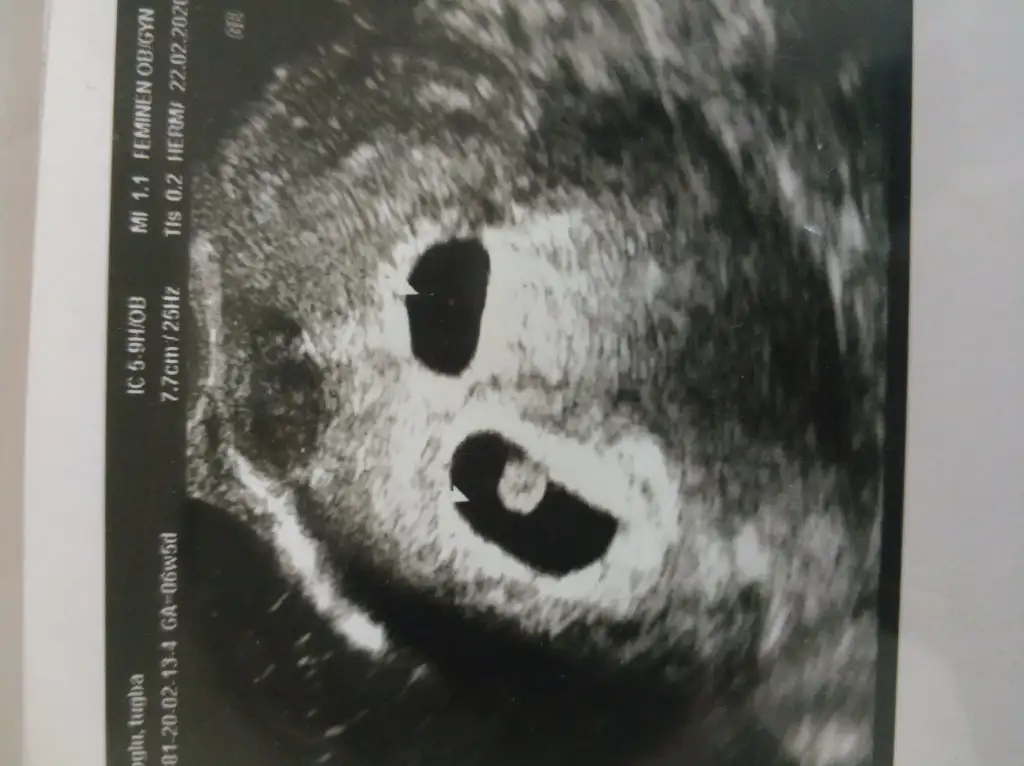

Önümüzdeki hafta hepimiz güzel haberlerle doldururuz burayı inşallah. Benim yarın sabah kalp sesini dinlemek için randevum var ama kalp sesinin yanında kanama alanı azalmıştır inşallah diyorum

Benim kese sağda o zaman kız